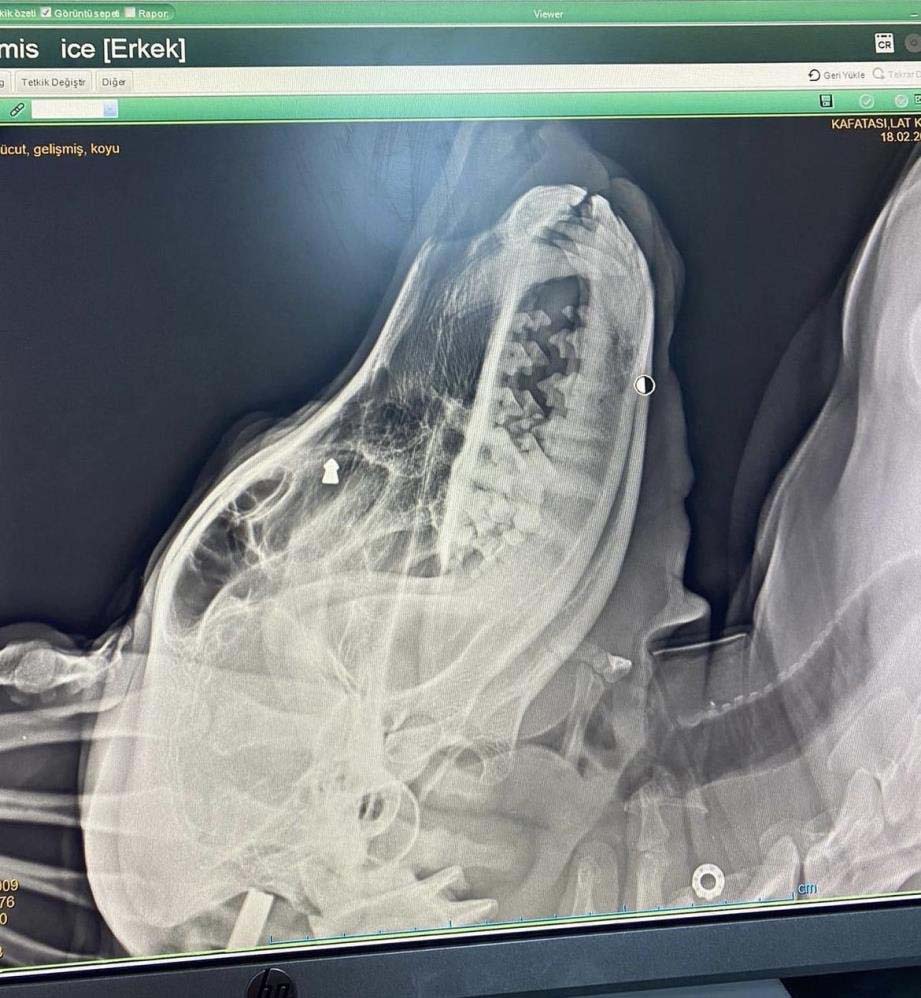

Olay, ilçenin İstasyon Mahallesi’nde meydana geldi. İddiaya göre, geçtiğimiz aylarda mahallede dolaşan sokak köpeğine, aracında oturan F.K. adlı kişi silahla ateş etti. Ciğerleri parçalanan köpek yol kenarına düştü. Çevredeki duyarlı vatandaşların ihbarı üzerine bölgeye polis ekipleri sevk edildi. Suçunu kabul eden F.K. gözaltına alınırken, yaralı köpek ekipler tarafından veteriner kliniğine götürülerek tedavi altına alındı.